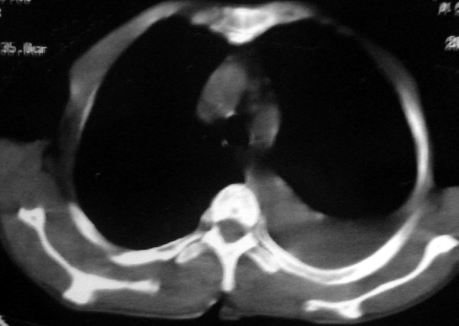

男,54岁,咳嗽,气喘半年,胸痛一月.

血性胸水

左侧胸腔积液 斜裂积液 心包积液 左肺不张 考虑左肺ca并胸膜心包转移。